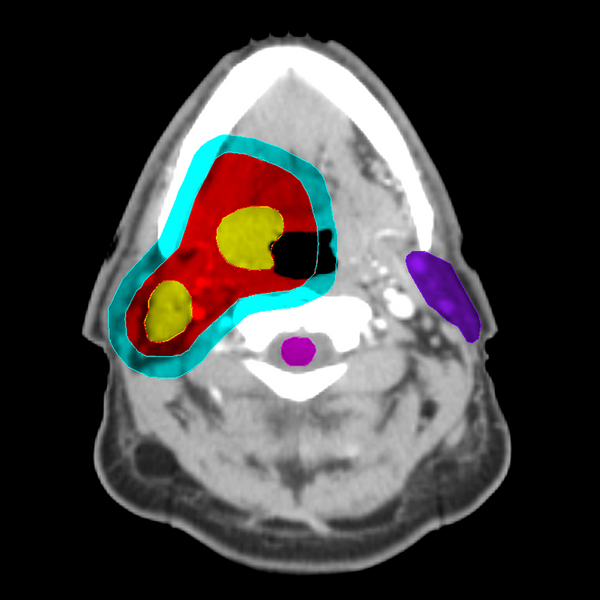

In this example, the dark purple area encompasses the parotid gland, one of the normal tissue

OARs (Organs at Risk) for radiation injury. The light purple color is a contour of the spinal cord, a second OAR.

The yellow shading indicates the GTV, again with the GTV consisting of two non-contiguous regions. The red area encompasses the CTV, and the light blue area the PTV.